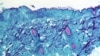

آبله میمون با علائمی مانند آنفولانزا شروع می‌شود و سپس به صورت التهاب پوستی خود را نشان می‌دهد.